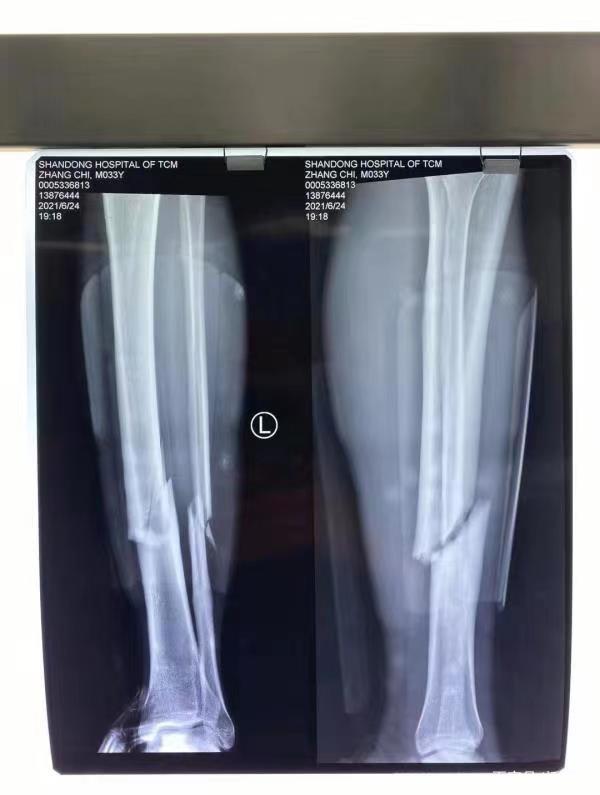

随后直接抬走,送去医院。在此过程中,张弛的表情一直比较痛苦,随后在医院的拍摄光片来看,正如队友的意料那样,小腿可能完全断裂。这样的消息,无疑让所有人心痛。随后众多的网友和球迷,纷纷在张弛和山东泰山的社交媒体下留言祝福,送去最美好的祈祷。

在10年前,当时山东鲁能泰山队和成都谢菲尔德的首轮中超联赛中,张弛就和李钢发生正面碰撞,导致左小腿完全变形,后经检查确认粉碎性骨折。年少就遭遇如此大的伤病,本以为就此会结束自己的职业生涯,但是经过长时间的恢复,张弛还是勇敢地站了起来,再次回到了赛场上。

而这次,张弛受伤的部位还是同一个位置,并且看上去也是比较严重,如今对于一个34岁的老将来说,可谓致命的打击。恢复起来的时间,也许需要更久,但是状态还能否达到昔日的巅峰,也是一个未知,甚至不排除就此退役的可能性,这无疑是谁都不愿意看到的结果。